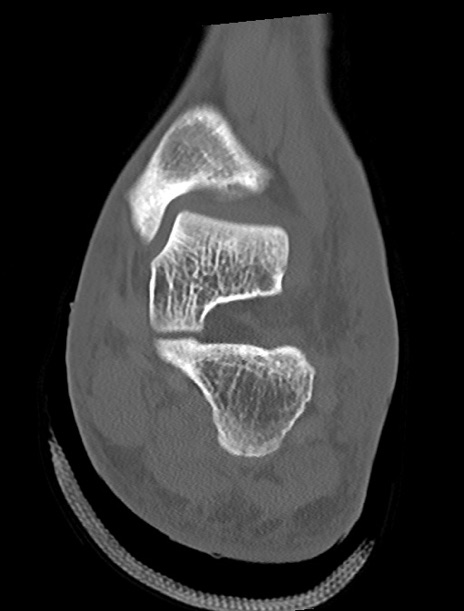

症例37 左足関節CT(冠状断像)

左足関節CT

矢状断像